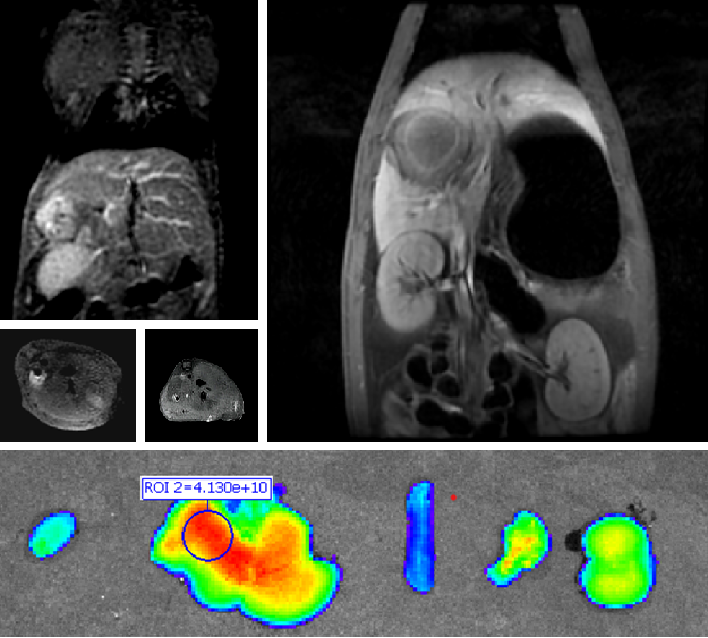

创新双模态造影剂(PL002)

太阳成集团tyc122ccvip自主研发的双模态造影剂PL002,已经获得美国FDA临床试验批件。PL002的研制首次提出通过整合磁共振技术,弥补现有荧光染料假阳性率高、透射深度有限等的短板,进而提升手术的精确性,降低手术过程中的风险,是全球首个获批临床试验的荧光/磁共振双模态造影剂。本项目预示着海南普利在造影剂领域的长期投入,并致力于开展独具特色的差异化国际化创新发展路径。